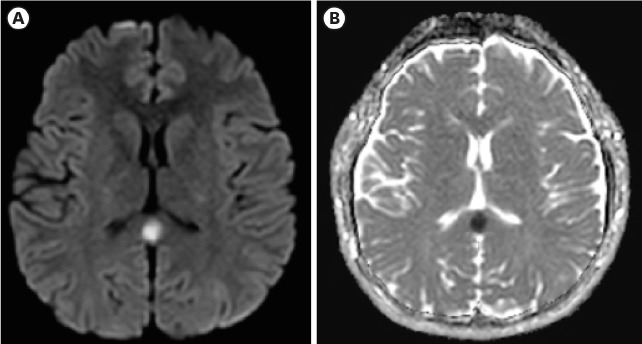

A 22-year-old previously healthy man visited the emergency department. He received the first dose of SARS-CoV-2 mRNA vaccine (BNT162b) 3-days prior coming to the hospital. He complained of febrile sensation and headache around the eyes and forehead. Upon admission, he was alert and neurologic examination showed that cranial nerves were grossly intact with both deep tendon reflexes and muscle strength being normal. There were signs of suspicious mild nuchal rigidity but not evident. SARS-CoV-2 polymerase chain reaction (PCR) that was performed due to fever turned out to be negative. Initial chemistry results showed leukopenia (3200/uL) and thrombocytopenia (141000/uL) with serum sodium being in the normal range (142mmol/L). There was no pleocytosis (WBC 2/uL) or other abnormalities in the CSF study. The patient's brain magnetic resonance imaging (MRI) showed an oval shaped restricted diffusion in the corpus callosum with low apparent diffusion coefficient (ADC) values and lack of contrast mediated enhancement (Fig. 1). He was transferred to a tertiary hospital emergency department and admitted, being diagnosed with cytotoxic lesion of the corpus callosum (CLOCCs) after SARS-CoV-2 mRNA vaccination. After that, the patient's symptoms improved and he was discharged 2 days later with no notable changes to be mentioned in the following outpatient check-up a week later.